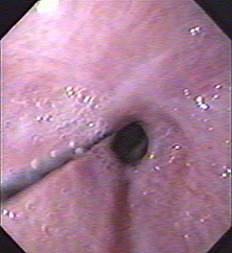

К сожалению, в большинстве случаев из-за выраженного стеноза эндоскоп удается довести только до верхнего края стриктуры. При этом струна вводится в сужение под визуальным контролем, но дальнейшее ее продвижение осуществляется вслепую, ориентируясь на свободное скольжение проводника и отсутствие болевых ощущений у больного (рис. 4 а, б).

Рис. 4 а, б. Проведение направляющей струны под контролем верхнего края ожоговой стриктуры пищевода (схема и эндофото)